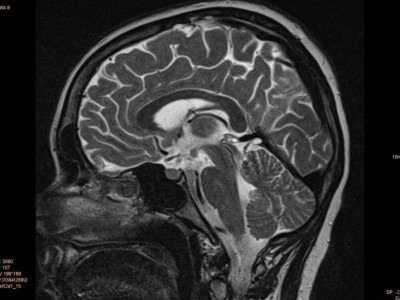

Fieberhafte Infektion, dann Ataxie und Kreislaufinsuffizienz

Eine neutropenische Jugendliche mit AML wird wegen eines fieberhaften Infekts aufgenommen. Ihr Zustand wird immer kritischer: Es kommt zu ausgeprägter Abnahme des Kurzzeitgedächtnisses, Kribbelparästhesien, Ataxie, schließlich Kreislaufinsuffizienz und Atemdepression. Das initial stark adipöse Mädchen hatte innerhalb von 6 Wochen ca. 18 kg Gewicht verloren. Ihre Diagnose?

CT-Befund des Thorax/© Prof. A.- J. Lemke, Zentrum für Radiologie, Gesundheit Nord gGmbH, Bremen, mit freundlicher Genehmigung , Koloskopie/© Kzenon / stock.adobe.com (Symbolbild mit Fotomodellen), Thrombozytopenie/© Kreipe, H. / all rights reserved Springer Medizin Verlag GmbH, Echoarmen Lymphknotenmetastase ohne Mark-Rinden-Struktur im Ultraschall/© Wihlfahrt K et al. / all rights reserved Springer Medizin Verlag GmbH, Patientin schaut besorgt auf Infusionsbeutel/© KatarzynaBialasiewicz / Getty Images / iStock (Symbolbild mit Fotomodellen), Zytologie mit Plasmazellen/© David A Litman / stock.adobe.com, Mit Schuhen auf Körperwaage/© Africa Studio / Stock.adobe.com (Symbolbild mit Fotomodell), Histopathologischer Befund bei akuter myeloischer Leukämie/© National Cancer Institute/cancer.gov, Einer Frau wird eine Infusion gelegt/© stephm2506 / stock.adobe.com, Röntgenassistentin bedient Röntgengerät/© nicoletaionescu / Stock.adobe.com (Symbolbild mit Fotomodell), Frau hält Kapseln in der Hand/© diego cervo / stock.adobe.com, Kraniales MRT/© Dr. Müller-Abt, Kinderradiologie, Olgahospital Stuttgart (Mit freundl. Genehmigung, alle Rechte vorbehalten), Search Icon, Blutabstrich der chonisch lymphatischen Leukämie/© jarun011 / Getty Images / iStock, Endoskopische Befunde des Magenkarzinoms/© Probst, A., Messmann, H. / all rights reserved Springer Medizin Verlag GmbH, Hand hält Laborröhrchen/© Kunstzeug / stock.adobe.com (Symbolbild mit Fotomodell), Radiologin richtet Mammographiescreening ein/© LIGHTFIELD STUDIOS / stock.adobe.com (Symbolbild mit Fotomodellen)